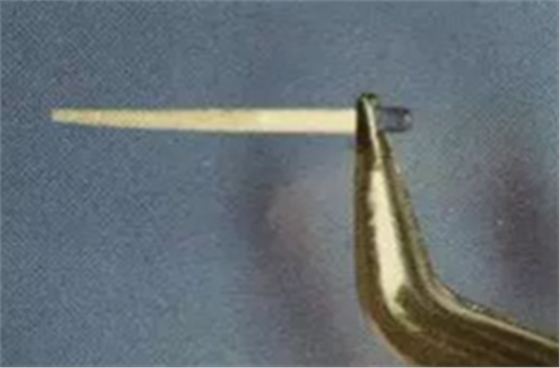

(鑷子夾持(正確))

(污染手套夾持(錯(cuò)誤))

(技工鉗裁剪(錯(cuò)誤))

試放后應(yīng)按所需長度用細(xì)粒金剛砂車針切割裁剪。

(粘樁堆核固化后裁剪)

為防止裁剪過程中有可能造成樁表面的污染,可以粘結(jié)固位后再進(jìn)行裁剪。